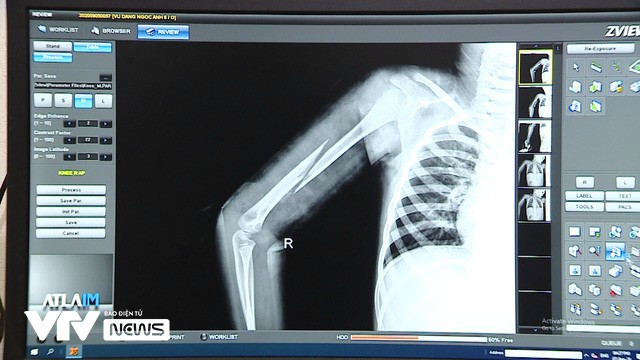

Sau khi được giải cứu thành công tại căn nhà của bố đẻ mình, cháu Đ.N.A, sinh năm 2014 (con gái của Đặng Trung Kiên, sinh năm 1973, cùng ở khu phố Tân Lập) được đưa đến Trung tâm y tế thị xã Từ Sơn để điều trị vết thương. Hậu quả của những trận đòn roi từ chính bố đẻ và người tình từ nhiều lần trước đó đã khiến toàn thân cháu bé xuất hiện nhiều vết tím bầm, tụ máu... ở phần gáy, lưng và đùi. Kết quả chụp X-quang tại Trung tâm y tế thị xã Từ Sơn còn cho thấy cánh tay phải của cháu bị gãy lìa xương.

Theo bác sĩ Nguyễn Văn Đức, Phó Khoa ngoại tổng hợp, Trung tâm y tế thị xã Từ Sơn, cháu bé vào viện trong tình trạng bị hoảng hốt, sợ hãi sau khi trải qua một sang chấn tâm lý rất nặng nề. "Những chấn thương phần mềm sẽ phục hồi được. Phần xương bị gãy chúng tôi phải theo dõi thêm. Sau 1 tuần nữa, chúng tôi phải chụp lại, xem xương có di lệch hay không" - bác sĩ Đức cho biết.